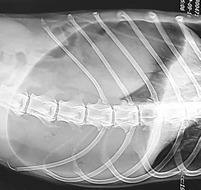

위 염전 증후군은 어떤 원인으로 인해 위장에 갑자기 가스가 차서 위장이 회전하고 비틀어 위장이나 주변 장기의 혈류를 차단하여 혈액 순환이 불가능하게 되어 발생합니다. 심한 경우에는 주변 장기의 괴사가 진행될 수 있으며 팽창된 위가 횡경막을 압박하여 호흡이 곤란해집니다. 심한 경우 사망에 이르는 치명적인 질병이다.

갑자기 침을 흘리고 구역질이 나는 등의 증상이 있으나 구토는 없고 위가 딱딱하게 부어오르고 일어설 힘이 없으며 호흡이 곤란해 보인다. 배에 가스가 차서 배를 두드리면 북소리가 난다.

위 염전 증후군의 치료는 가능한 한 빨리 수술하는 것입니다. 단순히 배에 가스가 찬 경우에는 내시경으로 간단히 가스를 제거하면 혈액순환이 회복된다. 그러나 배가 뒤집히면 그때부터 개의 생사의 문제가 된다. 위가 돌아오면 병원에서는 단순히 가스를 빼는 것이 아니라 배를 열어 가스를 제거한 뒤 위를 원래 위치로 되돌린 뒤 위를 복벽에 고정하는 수술을 해서 재발을 방지해야 한다.